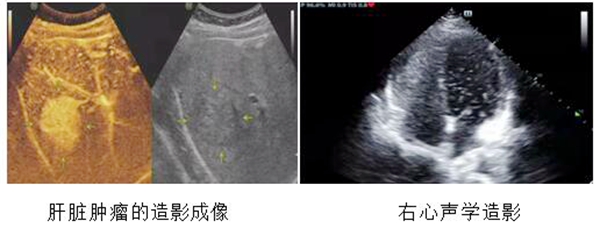

3、 超声造影成像技术

是利用超声造影剂使后散射回声增强,以明显提高超声诊断的分辨力、敏感性和特异性技术。

超声造影原理:超声造影剂之所以具有显影作用是是因为造影剂微泡内含有气体,微泡直径较小(90%直径小于6μm),与红细胞大小(7μm)相当,可以作为血管的示踪剂。微泡与血液构成气-液界面,并与组织构成气-组织界面,形成许多新的声学界面,从而产生造影效果。通过观察造影剂的行踪及其分布情况,可对病变进行诊断和鉴别诊断。

超声造影的优点:超声造影剂可通过呼吸排出,肾衰竭及肝功能异常等患者仍可进行超声造影;不需皮试,可经外周静脉或腔内注射;能用于全身实质性脏器,是一种纯血池造影剂,不会外渗到组织间隙;超声检查方便,快速,短时间内可重复多次;能持续观察造影过程。

可应用于消化系统、泌尿系统、眼部、浅表器官(如腮腺、乳腺、甲状腺等)等部位肿瘤的鉴别诊断;肿大淋巴结的良恶性诊断;肝脏转移瘤及肝硬化结节的鉴别诊断;子宫、输卵管造影的评价:检测输卵管通畅度;介入手术疗效评估;监测肿瘤生物、化学、放射治疗的疗效;心脏内血流分流的情况;动脉粥样斑块的稳定性判断;四肢血管方面可准确诊断血管狭窄、栓塞以及血管畸形等病变。